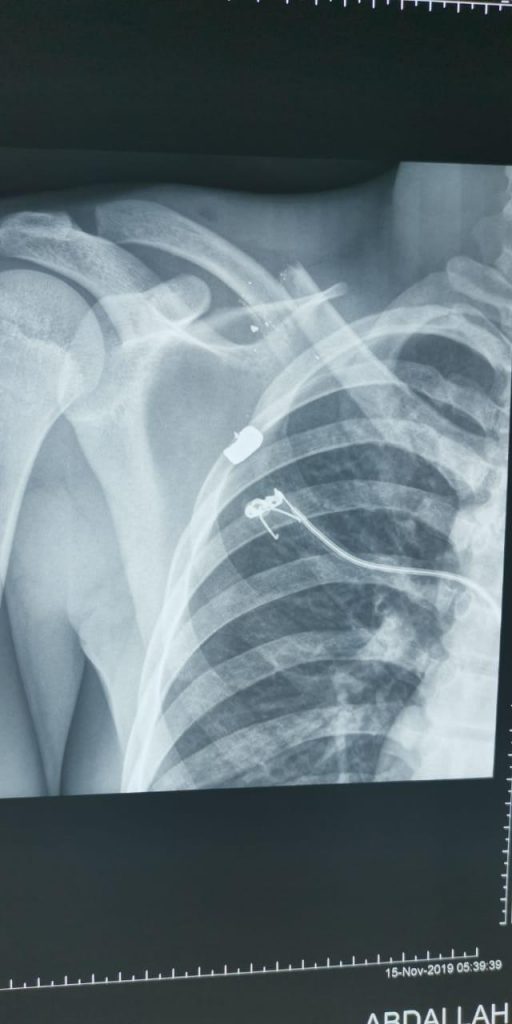

فريق طبي ينجح في تثبيت الترقوة جراحيا في مستشفى القويعية العام

نجح فريق طبي في مستشفى القويعية العام، في اجراء اول عملية تثبيت كسر ترقوة مضاعف، وتعد الأولى من نوعها في المستشفى.ويأتي الإنجاز الطبي الجديد برئاسة عبر استشاري العظام الدكتور محمود ابو عيطه والذي باشر حديثا ...